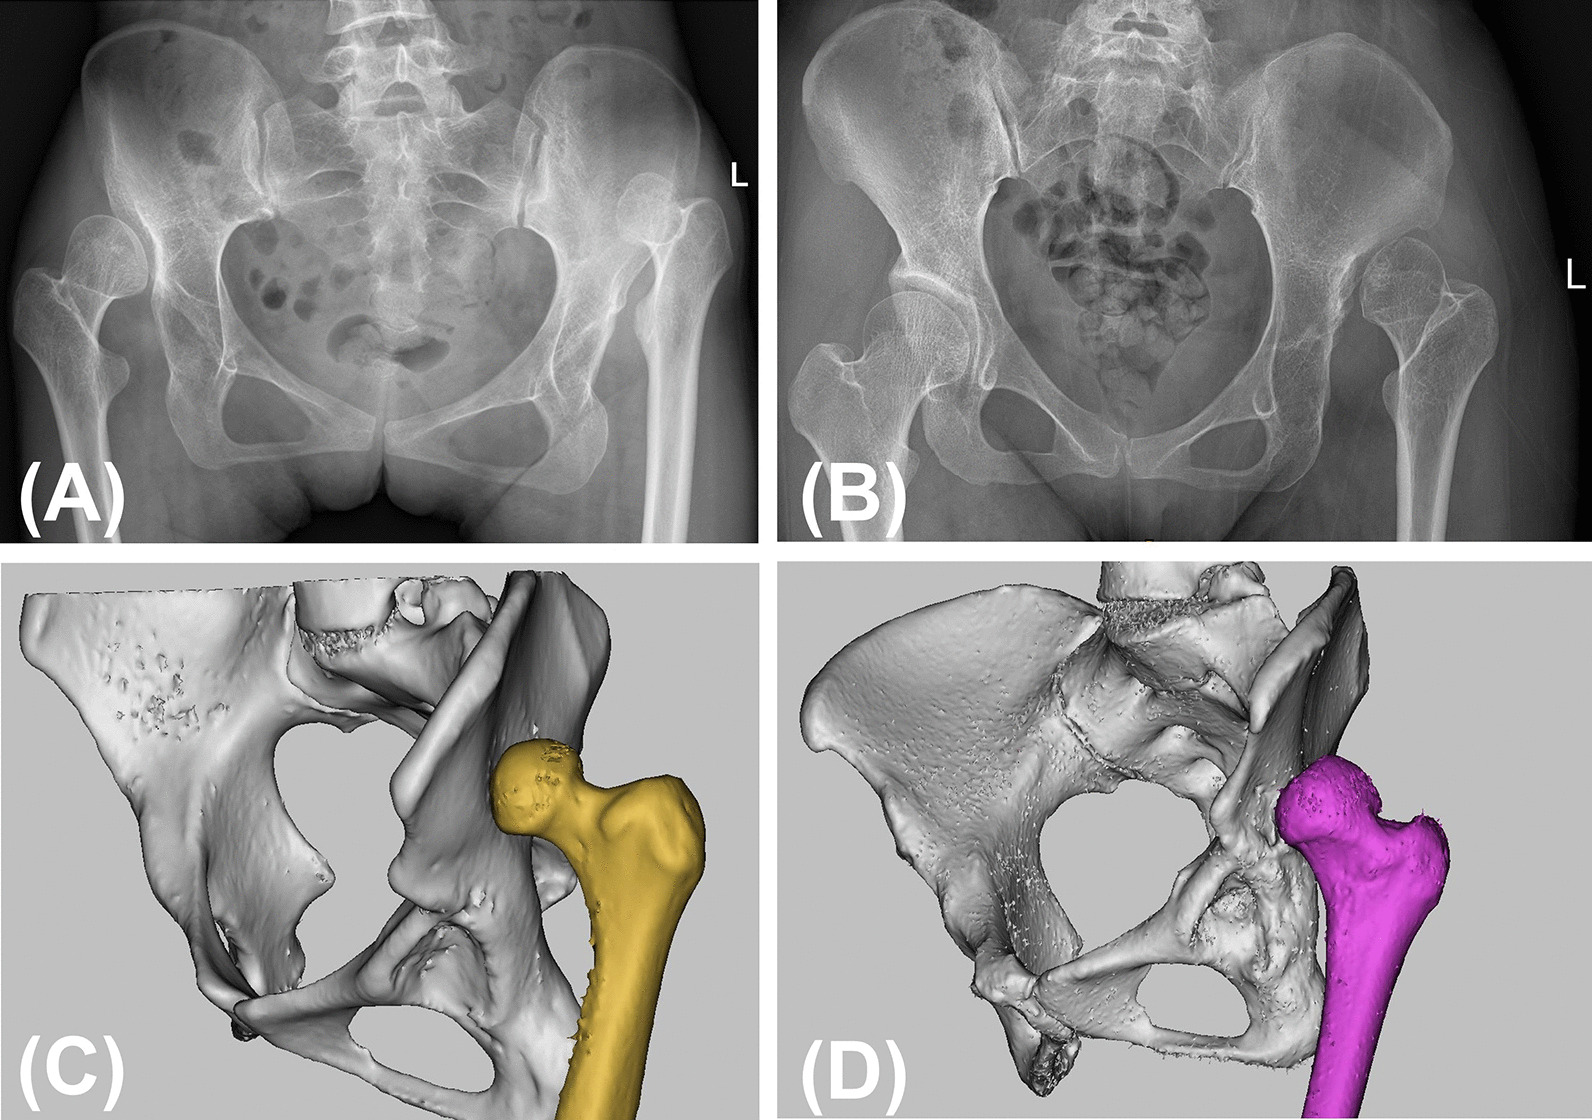

The study was approved by the institutional review board of Guangdong Provincial People’s Hospital (IRB: 2019528HR1). We retrospectively reviewed the preoperative imaging data of 352 patients (496 hips) with DDH between January 2009 and January 2019. According to the Crowe classification, 52 patients (60 hips) were graded as type IV DDH on standing anteroposterior pelvic radiographs. The height of the dislocation was measured on standard AP plain radiographs and was defined as the vertical distance between the head-neck junction and the line connecting the lower edges of the bilateral teardrops. The exclusion criteria included (1) patients who underwent prior hip surgery; (2) patients with a dislocation attributed to infection or trauma; and (3) patients who did not have preoperative CT data or had substandard CT data. Thus, 51 dysplastic hips in 45 patients met the inclusion criteria and were retrospectively evaluated. The included patients were further divided as follows: group IVa, a dislocated femoral head located within the abductor muscle mass, and group IVb, evidence of the formation of a false acetabulum (Fig. 1). Herein, 25 hips were included in the IVa group and 26 hips were included in IVb group, with 3 patients affected by bilateral Crowe type IV DDH in each group. Fifteen patients (30 hips) without hip disease or deformities who had undergone computed tomography angiography (CTA) to diagnose vascular diseases were chosen as controls. Demographic data for the subjects are shown in Table 1.

Fig. 1.

AP radiograph and 3D model two types of Crowe IV DDH. A, C A 22-year-old female patient in Crowe type IVa group (L: IVa, R: III). B, D A 30-year-old female patient in Crowe type IVb group (L: IVb)